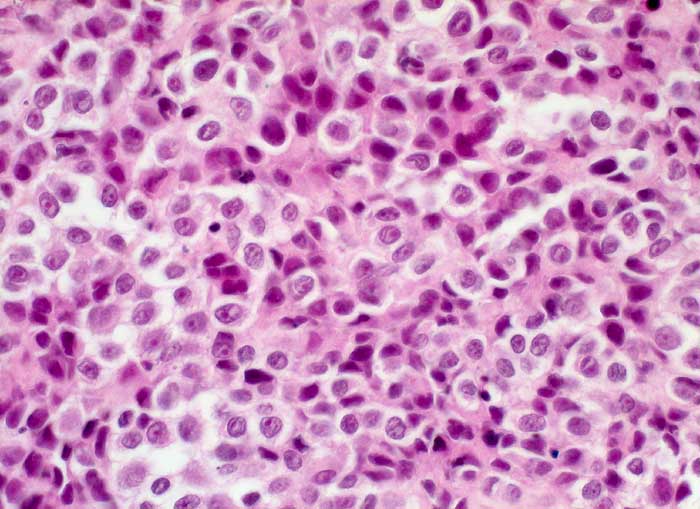

Maligner Pleuraerguss: Malignes Melanom

Diagnose Gruppe

maligner Tumor

Pleuraerguss Zytologie

Der Nachweis von eisennegativem Pigment und die Positivität für den melanozytären Marker HMB-45 in malignen Zellen bestätigt die Diagnose eines malignen Melanoms.